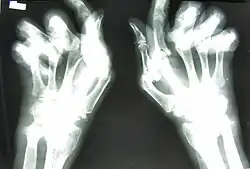

![]() Dłonie pacjentów ze zmianami w przebiegu RZS |

Występuje ból i obrzęk zajętych stawów z ograniczeniem ich ruchomości. Charakterystycznym objawem jest sztywność poranna stawów, ustępująca stopniowo podczas ruchu. Jest to silny ból stawów oraz ich sztywność i obrzęk, które uniemożliwiają wykonywanie nawet najprostszych czynności, takich jak mycie, ubieranie czy swobodne poruszanie się. Symptom ten powoduje uczucie silnej bolesności przy próbie ściśnięcia dłoni i ograniczenie możliwości ruchu. Długość trwania sztywności zależy od nasilenia procesu zapalnego[9] - może trwać od kilku minut do kilkunastu godzin. Wcześnie dochodzi do zaników mięśni międzykostnych, glistowatych i mięśni kłębu kciuka. Maleje siła mięśni, siła i pewność chwytu dłoni. Często występuje zajęcie ścięgien i pochewek ścięgnistych. Uszkodzenie stawu i aparatu więzadłowego powoduje charakterystyczne odgięcie łokciowe (ulnaryzację) palców ręki, podwichnięcie dłoniowe paliczków dalszych, zmiany typu łabędziej szyjki i palca butonierkowego; może dojść do przeprostów. Powikłaniem może być również powstanie torbieli Bakera.

- typowe dla RZS zmiany w RTG (nadżerki, osteoporoza)

- okres I – wczesny – w badaniu RTG widoczne obrzęki tkanek miękkich, niewielkie zwężenie szpar stawowych, osteoporoza przynasadowa, ból, obrzęk, pogrubienie zarysu stawów, sztywność poranna;

- okres II – zmiany umiarkowane – ww. objawy plus zmiany okołostawowe: zaniki mięśniowe, głównie mięśni międzykostnych, mięśni glistowatych ręki, mięśni czworogłowych uda, ruchomość ograniczona, w RTG wyraźna osteoporoza, mogą być pierwsze objawy uszkodzenia chrząstki, wyraźne zwężenie szpar stawowych, w częściach przynasadowych kości widoczne geody zapalne oraz pojedyncze nadżerki na powierzchniach stawowych;

- okres III – zmiany zaawansowane – okres najbardziej widoczny, obecne trwałe uszkodzenia, ww. objawy bardziej nasilone, zmiany w narządach wewnętrznych, rozwój geod i nadżerek, podwichnięcia i zniekształcenia stawów, w RTG wyraźna osteoporoza, uszkodzenia chrząstki i kości;

- okres IV – faza schyłkowa – ww. objawy plus zrosty włókniste i całkowite zesztywnienie kostne stawu